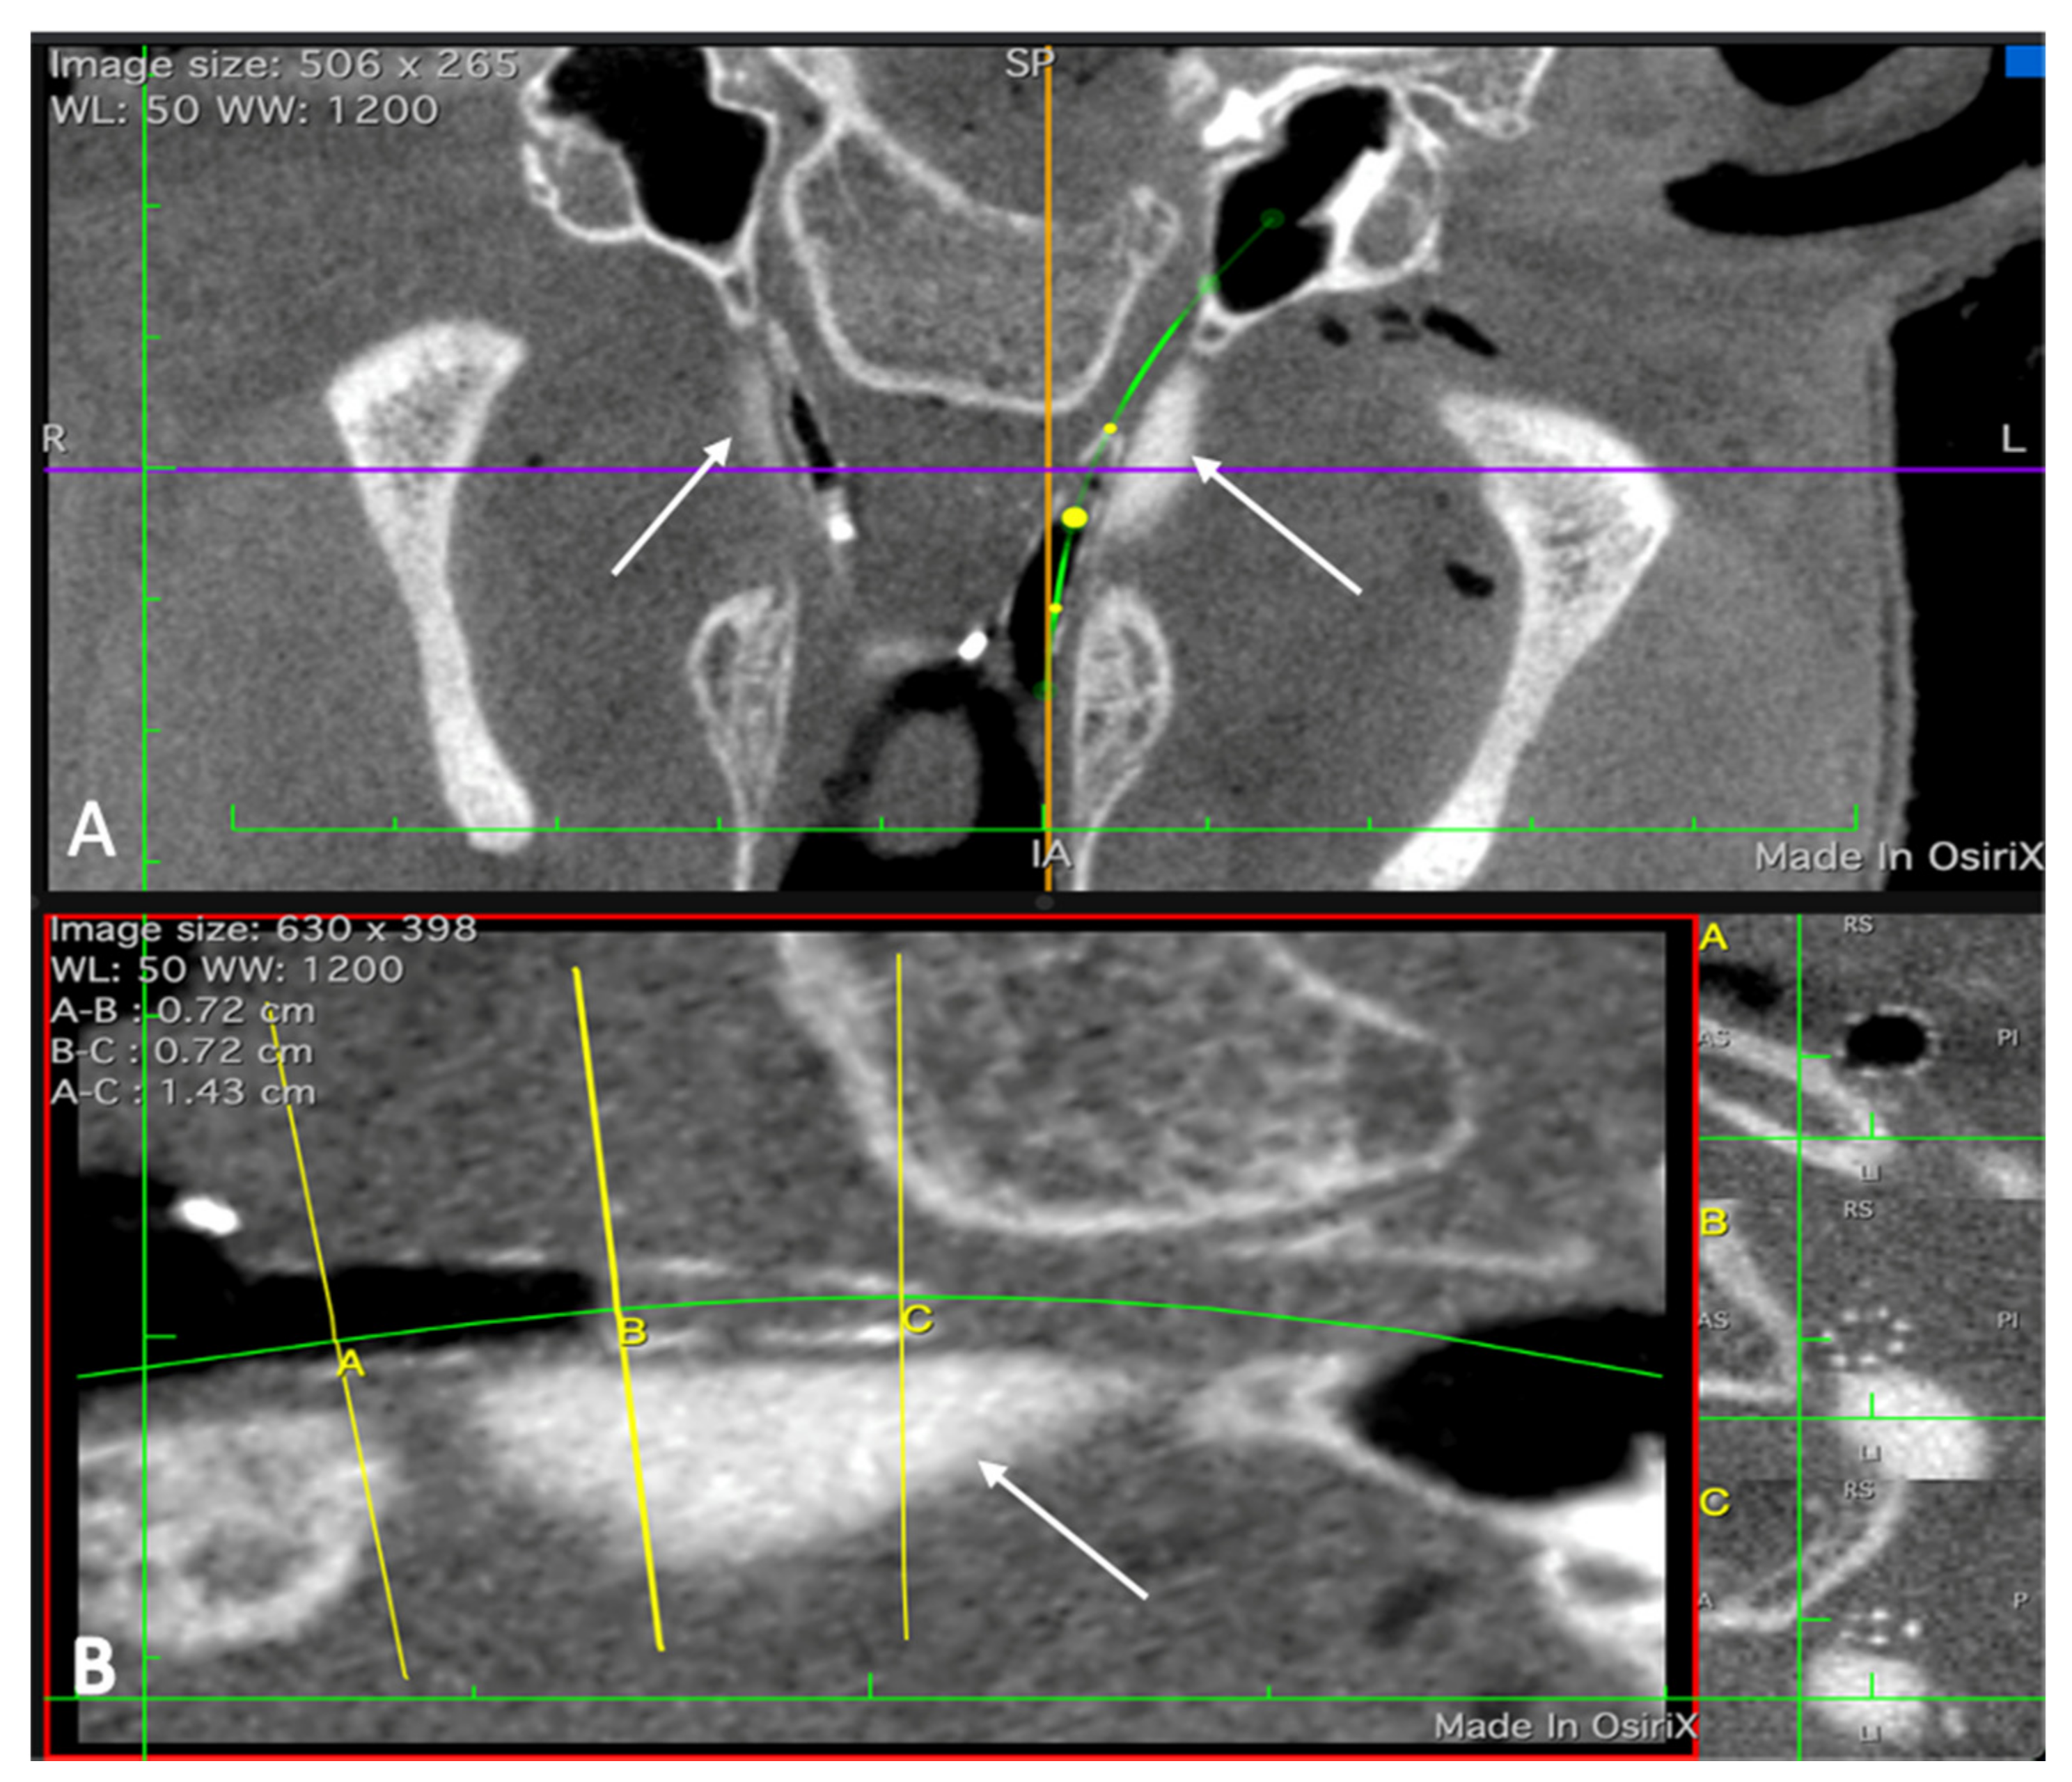

3.2.4. Imaging